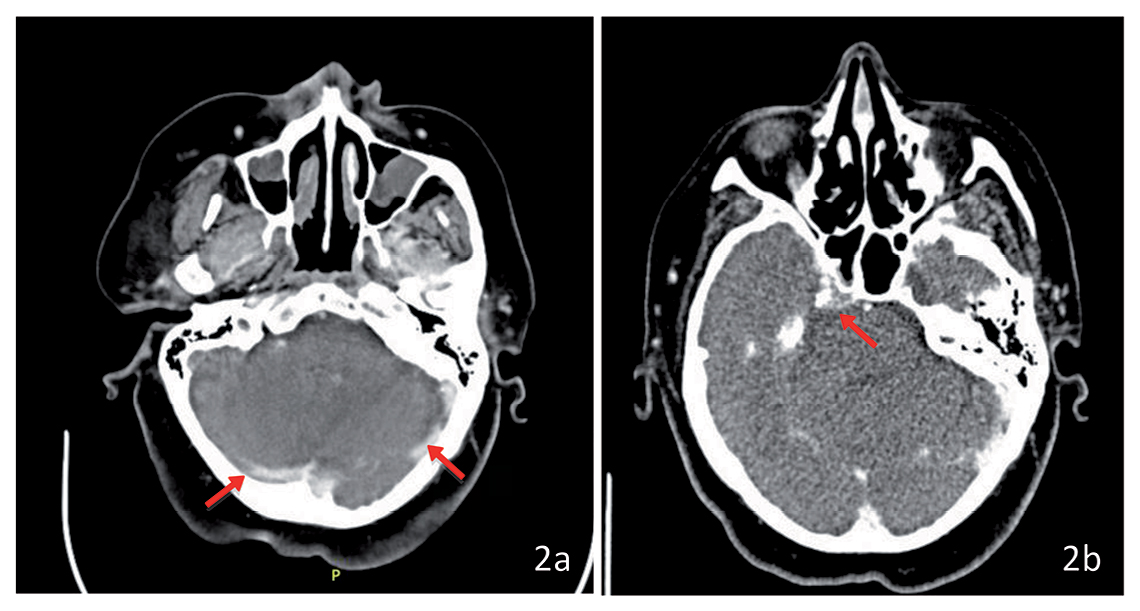

Se realiza angiotomografía craneal y cervical, que revela gran masa cervical derecha de origen tiroideo con realce heterogéneo de 95 x 67 x 82 mm, la cual compromete músculos esternocleidomastoideo y platisma, desplazando la tráquea (Figura 1). Adenopatías cervicales GI y GIIa de hasta 11 mm, trombosis del seno transverso, sigmoideo (Figura 2a) y vena yugular derecha. Lesiones líticas en región pretroclival de 17 mm que contacta región posterior de seno cavernoso y canal medular (Figura 2b). Tomografía de tórax: 5 nódulos pulmonares indeterminados de 3-4 mm, adenopatías cervicales inferiores, retrotraqueales y masa tiroidea previamente descrita que se extiende hacia tórax. Estudio tiroideo: TSH 4,47 ulU/ml; T4 Libre 1,24 ng/dl, anticuerpo antitiroglobulina 25 UD OMS y tiroglobulina 763 ug/L.

Figura 2. Corte axial de TAC de encéfalo; a: Trombosis del seno transverso y sigmoideo (indicado mediante flechas rojas); b: Compromiso osteolítico de región petroclival (indicado con flecha roja).